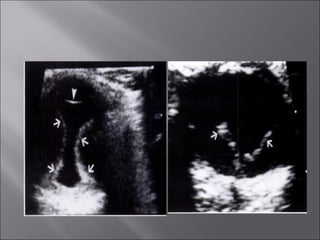

Ultrasound and CT scans provide anatomical images of the orbit, while color Doppler imaging provides visualizations of vascular structures and blood flow within lesions. These imaging techniques are used to evaluate a variety of orbital conditions involving blood vessels, infections, tumors, congenital issues, trauma, and more, and can help identify vascular disorders, thrombosis, treatment responses, and dynamic changes in benign tumors over time.